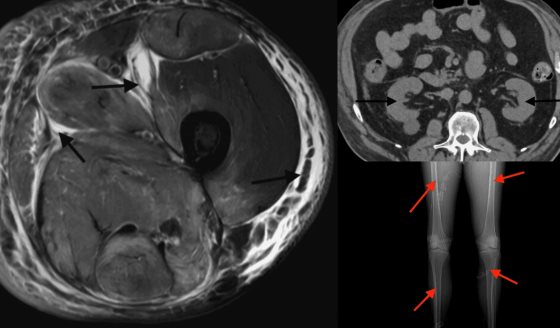

El Dr. Salinas explicó que para el caso de Jeison se utilizó una técnica poco común en la práctica clínica actual: el trasplante renal en bloque. Esta decisión respondió a las características particulares del donante y del receptor, cuya compatibilidad requería una intervención distinta a la convencional.

Aunque su uso es limitado, el trasplante en bloque ha resurgido como alternativa para ampliar el espectro de donantes disponibles. En el caso de Jeison, un joven de 19 años, el órgano provenía de un donante pediátrico de poco más de 30 kilos.

Debido al tamaño reducido de los riñones, el trasplante de un solo órgano no garantizaba la función renal adecuada, por lo que fue necesario implantar ambos en un solo procedimiento.

Respecto a los desafíos asociados a esta técnica, el especialista señaló que su uso es muy poco frecuente y presenta importantes dificultades desde el punto de vista técnico. En este caso, el donante por el peso del donante, complicaba las anastomosis debido a la corta longitud de los vasos sanguíneos y el tamaño reducido de los riñones. Además, Jeison es un paciente de baja estatura, lo que limitaba el espacio disponible en la región inguinal para realizar la intervención.

La oportunidad llegó con un donante pediátrico de menos de 30 kilos, lo que implicó una diferencia significativa con respecto al peso de Jeison, cercano a los 60 kilos. Ante ese panorama, la única opción viable fue un trasplante en bloque.